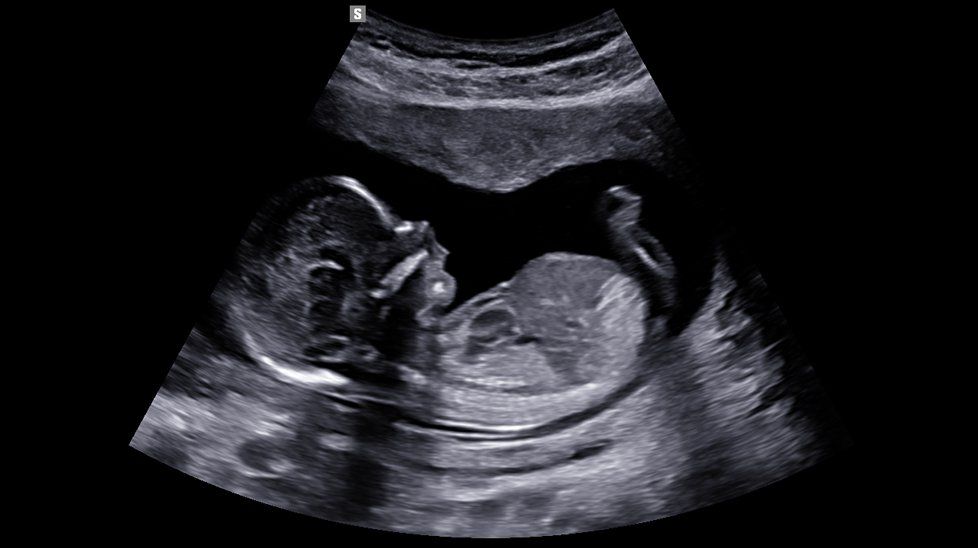

2.7. Nhiễu ảnh trong siêu âm do hiện tượng khúc xạ

Hiện tượng nảy xảy ra khi sóng siêu âm không thẳng góc với mặt ngăn cách của cấu trúc cần khảo sát. Ví dụ cụ thể là do hai cơ thẳng bụng đối xứng nhau sẽ làm 2 chùm tia từ 2 chấn tử của đầu dò thẳng hội tụ nhau tại một cấu trúc nào đó như động mạch chủ bụng hoặc tử cung. Kết quả là tạo nhiễu ảnh là hai bóng động mạch chủ, tử cung đôi hoặc đôi khi là 2 túi thai đối xứng nhau qua đường giữa.